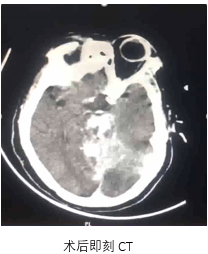

病历夹什么径技·第151期|串联营病历夹:京广连营_https://www.jmylbn.com_新闻资讯_第78张

病历夹什么径技·第151期|串联营病历夹:京广连营_https://www.jmylbn.com_新闻资讯_第79张

病历夹什么径技·第151期|串联营病历夹:京广连营_https://www.jmylbn.com_新闻资讯_第80张

<<滑动查看下一张图片>>

• 患者术后转入重症医学科,症状一直未有改善,昏迷状,术后第5天家属放弃治疗自动出院。